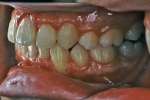

マルチブラケット終了時